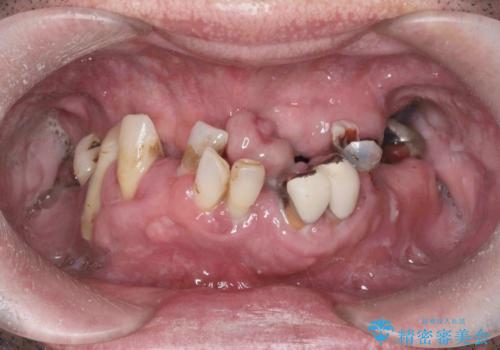

入れ歯掲載症例数57件